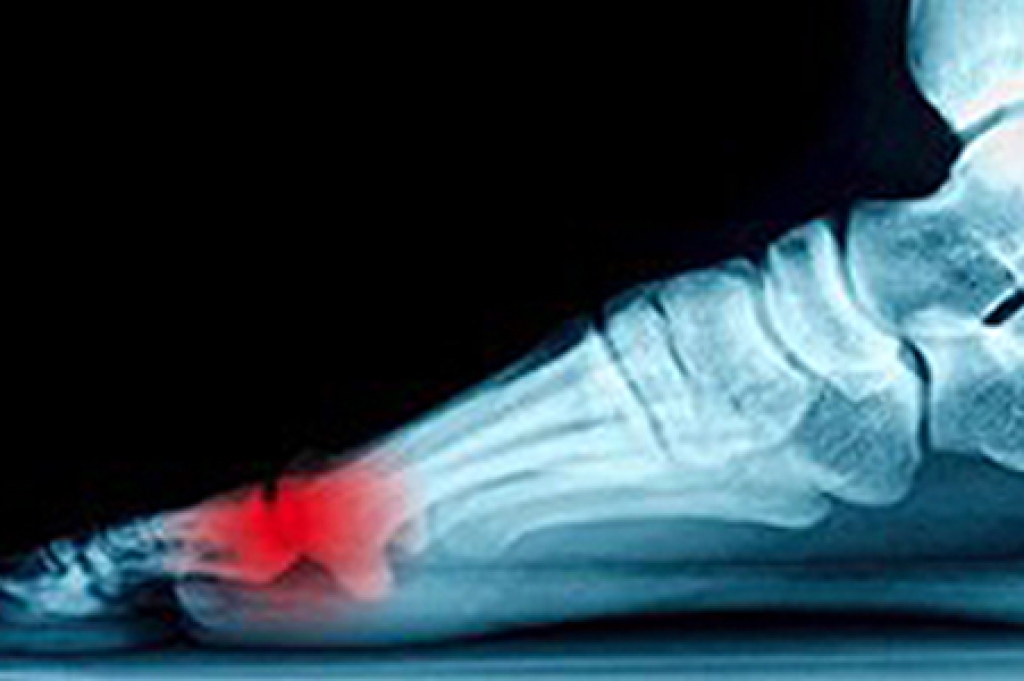

A foot ulcer is an open sore that can affect the surface skin or extend deep enough to reach tendons, bones, or other structures. People with diabetes, poor circulation, nerve damage, or foot deformities face a higher risk of developing ulcers. Nerve damage can make it hard to notice injuries like cuts or pressure spots, especially when wearing shoes that rub against the skin. Poor circulation slows healing by limiting the oxygen that reaches tissues in the foot. If left untreated, a foot ulcer may become infected, sometimes leading to an abscess, cellulitis, or a bone infection. In severe cases, it can cause tissue death or result in limb loss. Early care by a podiatrist focuses on diagnosing the cause of the ulcer, removing dead tissue, if needed, and helping to prevent infection. If you have developed a foot ulcer that will not heal, it is suggested that you schedule an appointment with a podiatrist for an exam and appropriate treatment options.

While it may not seem apparent with small ulcers on the foot, for diabetics, any size ulcer can become infected. Diabetics often also suffer from neuropathy, or nerve loss. This means they might not even feel when they have an ulcer on their foot. If the wound becomes severely infected, amputation may be necessary. Therefore, it is of the upmost importance to properly care for any and all foot wounds.